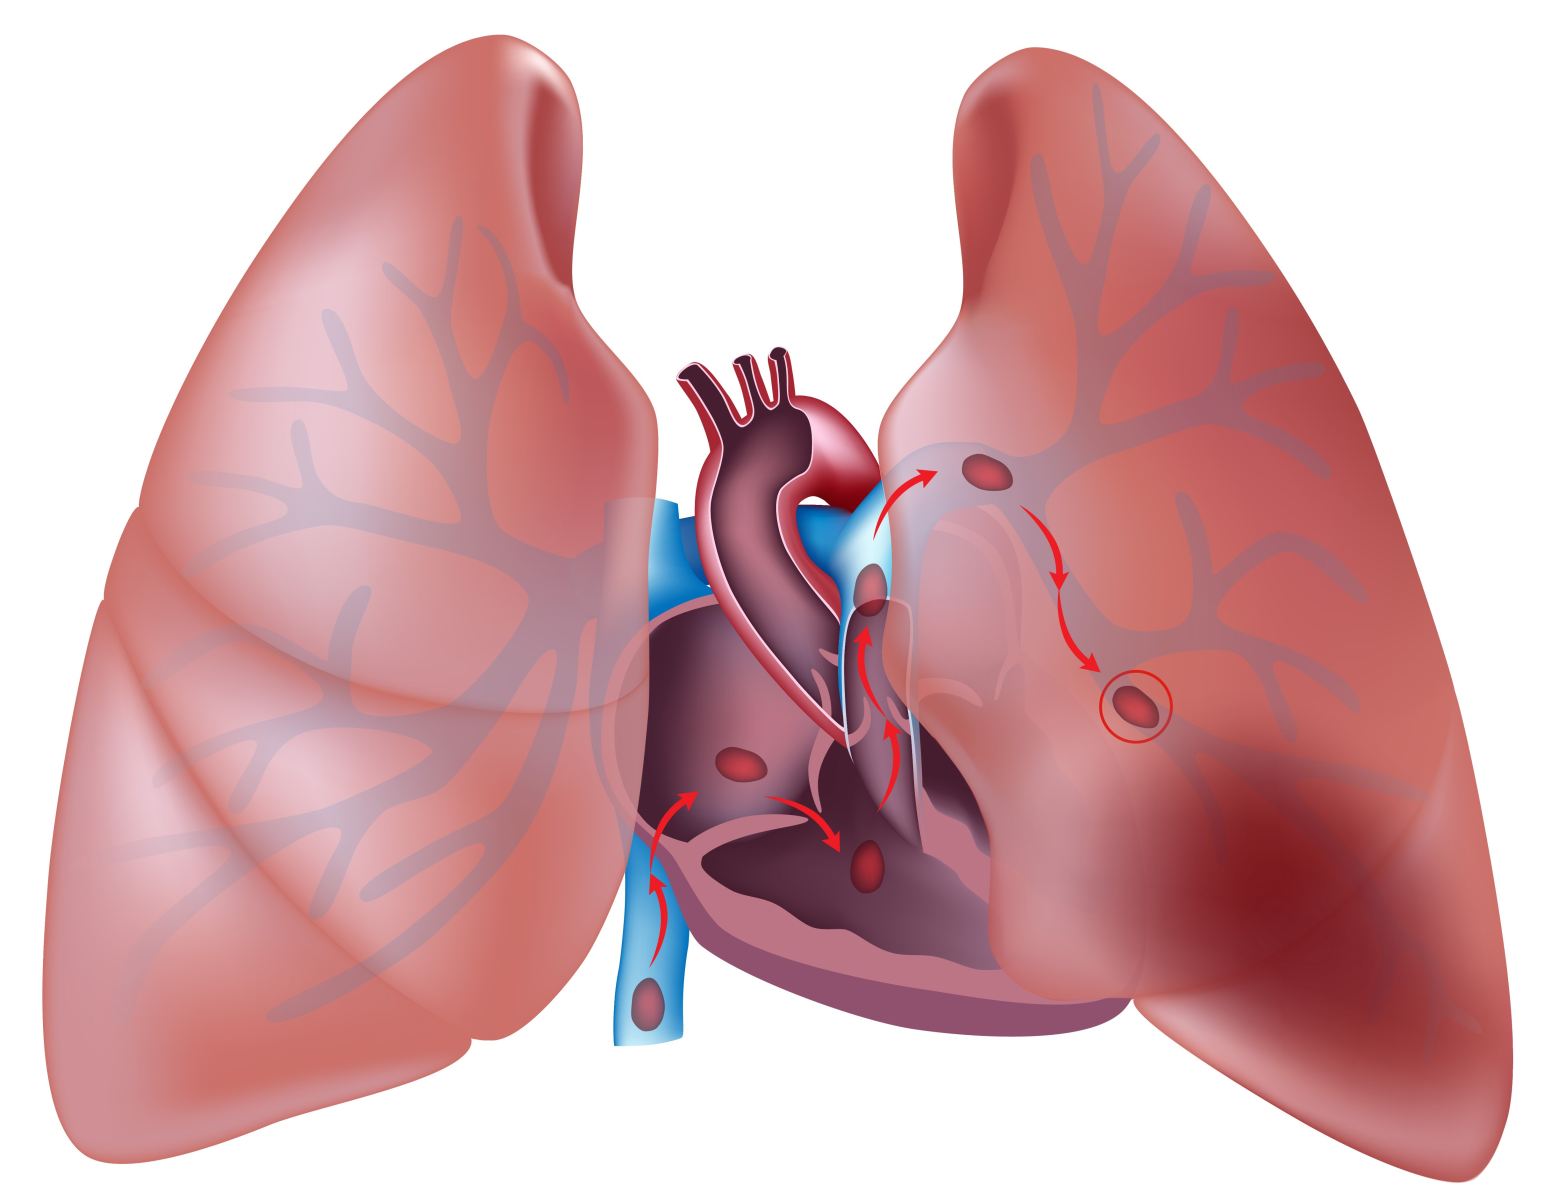

При патологии сердца тромбы в большинстве случаев образуются на внутренней поверхности ушка правого предсердия. Некоторое время они могут удерживаться в месте формирования, пока ток крови не оторвет их и не занесет в артерии малого круга кровообращения, благодаря которому легкие обеспечиваются кровью.

- тромбозы вен (чаще – глубоких) нижних конечностей;

- тромбофлебиты глубоких тазовых вен;

Кислородное голодание фрагмента легкого, случившееся из-за закупорки ветвей легочных артерий, приводит к тому, что клетки легочной ткани начинают повреждаться. Бывает, что из соседних участков легкого с нормальным кровоснабжением сюда устремляется кровь – развивается так называемая геморрагическая (кровяная) разновидность инфаркта легкого. К очагу поражения нередко устремляется инфекция, поэтому при инфаркте легкого может присоединиться так называемая инфаркт-пневмония, существенно осложняющая течение заболевания.